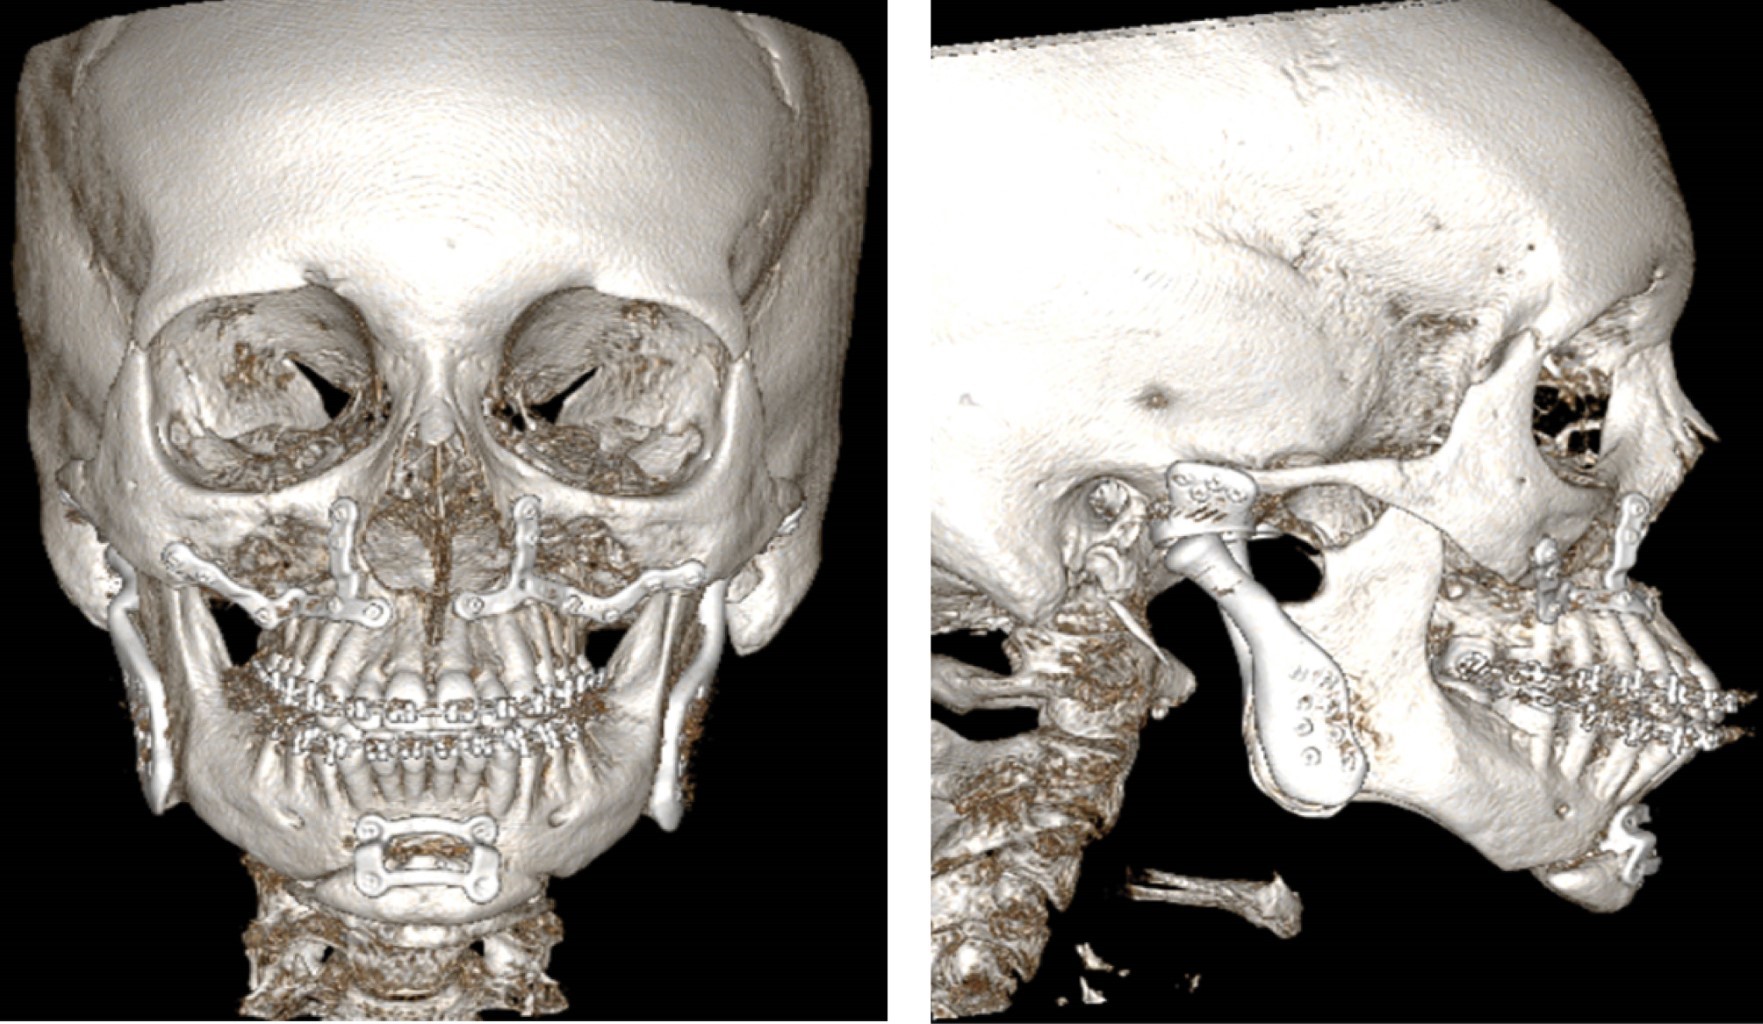

Se realiza planificación virtual con confección de prótesis customizadas y placas de osteosíntesis a medida (Raomed) (Figura 3).

El procedimiento, realizado bajo anestesia general y con monitoreo del nervio facial, incluyó los siguientes pasos: reemplazo articular bilateral mediante abordaje preauricular y submandibular, osteotomías tipo Le Fort I y mentoplastia, reposición y osteosíntesis con placas customizadas según planificación virtual.

Este enfoque quirúrgico integral buscó corregir la maloclusión y las deformidades esqueléticas (Figura 4), mejorando la proyección mandibular y aumentando el diámetro de la vía aérea (Figura 5), con el fin de lograr estabilidad articular y oclusal y de restituir la estética y la funcionalidad (Figuras 6 y 7).

Figura 3

Figura 4